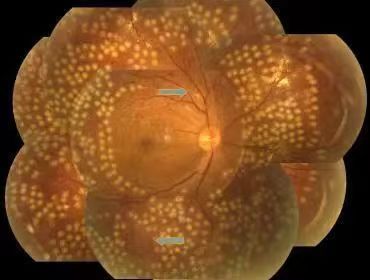

不同程度的糖尿病视网膜病变

视网膜激光光凝:采用激光的热凝效用,在局部出血部位和(或)无灌注区形成凝固激光斑,达到止血、预防再出血的效果。该治疗为增殖期病变的首选治疗方式,较早实行全视网膜光凝能有效预防失明,且价格低廉,效果较好。

激光光凝治疗

视网膜激光光凝术是治疗糖尿病性视网膜病变(DR)的重要手段,分为全视网膜激光光凝(PRP)、黄斑格栅样激光光凝等。激光光凝术是高危增殖性糖尿病性视网膜病变(DR)患者及某些严重非增殖性患者的主要治疗方式。

激光治疗旨在减少视力进一步下降的危险,尽量保护视功能。高危增殖性糖尿病性视网膜病变患者应迅速施行全视网膜激光光凝治疗。约50%的重度非增殖性糖尿病性视网膜病变患者在1年内可进展为增殖性糖尿病性视网膜病,15%进展为高危增殖性糖尿病性视网膜病,若病情进展应考虑行全视网膜激光光凝治疗。

全视网膜激光光凝术后